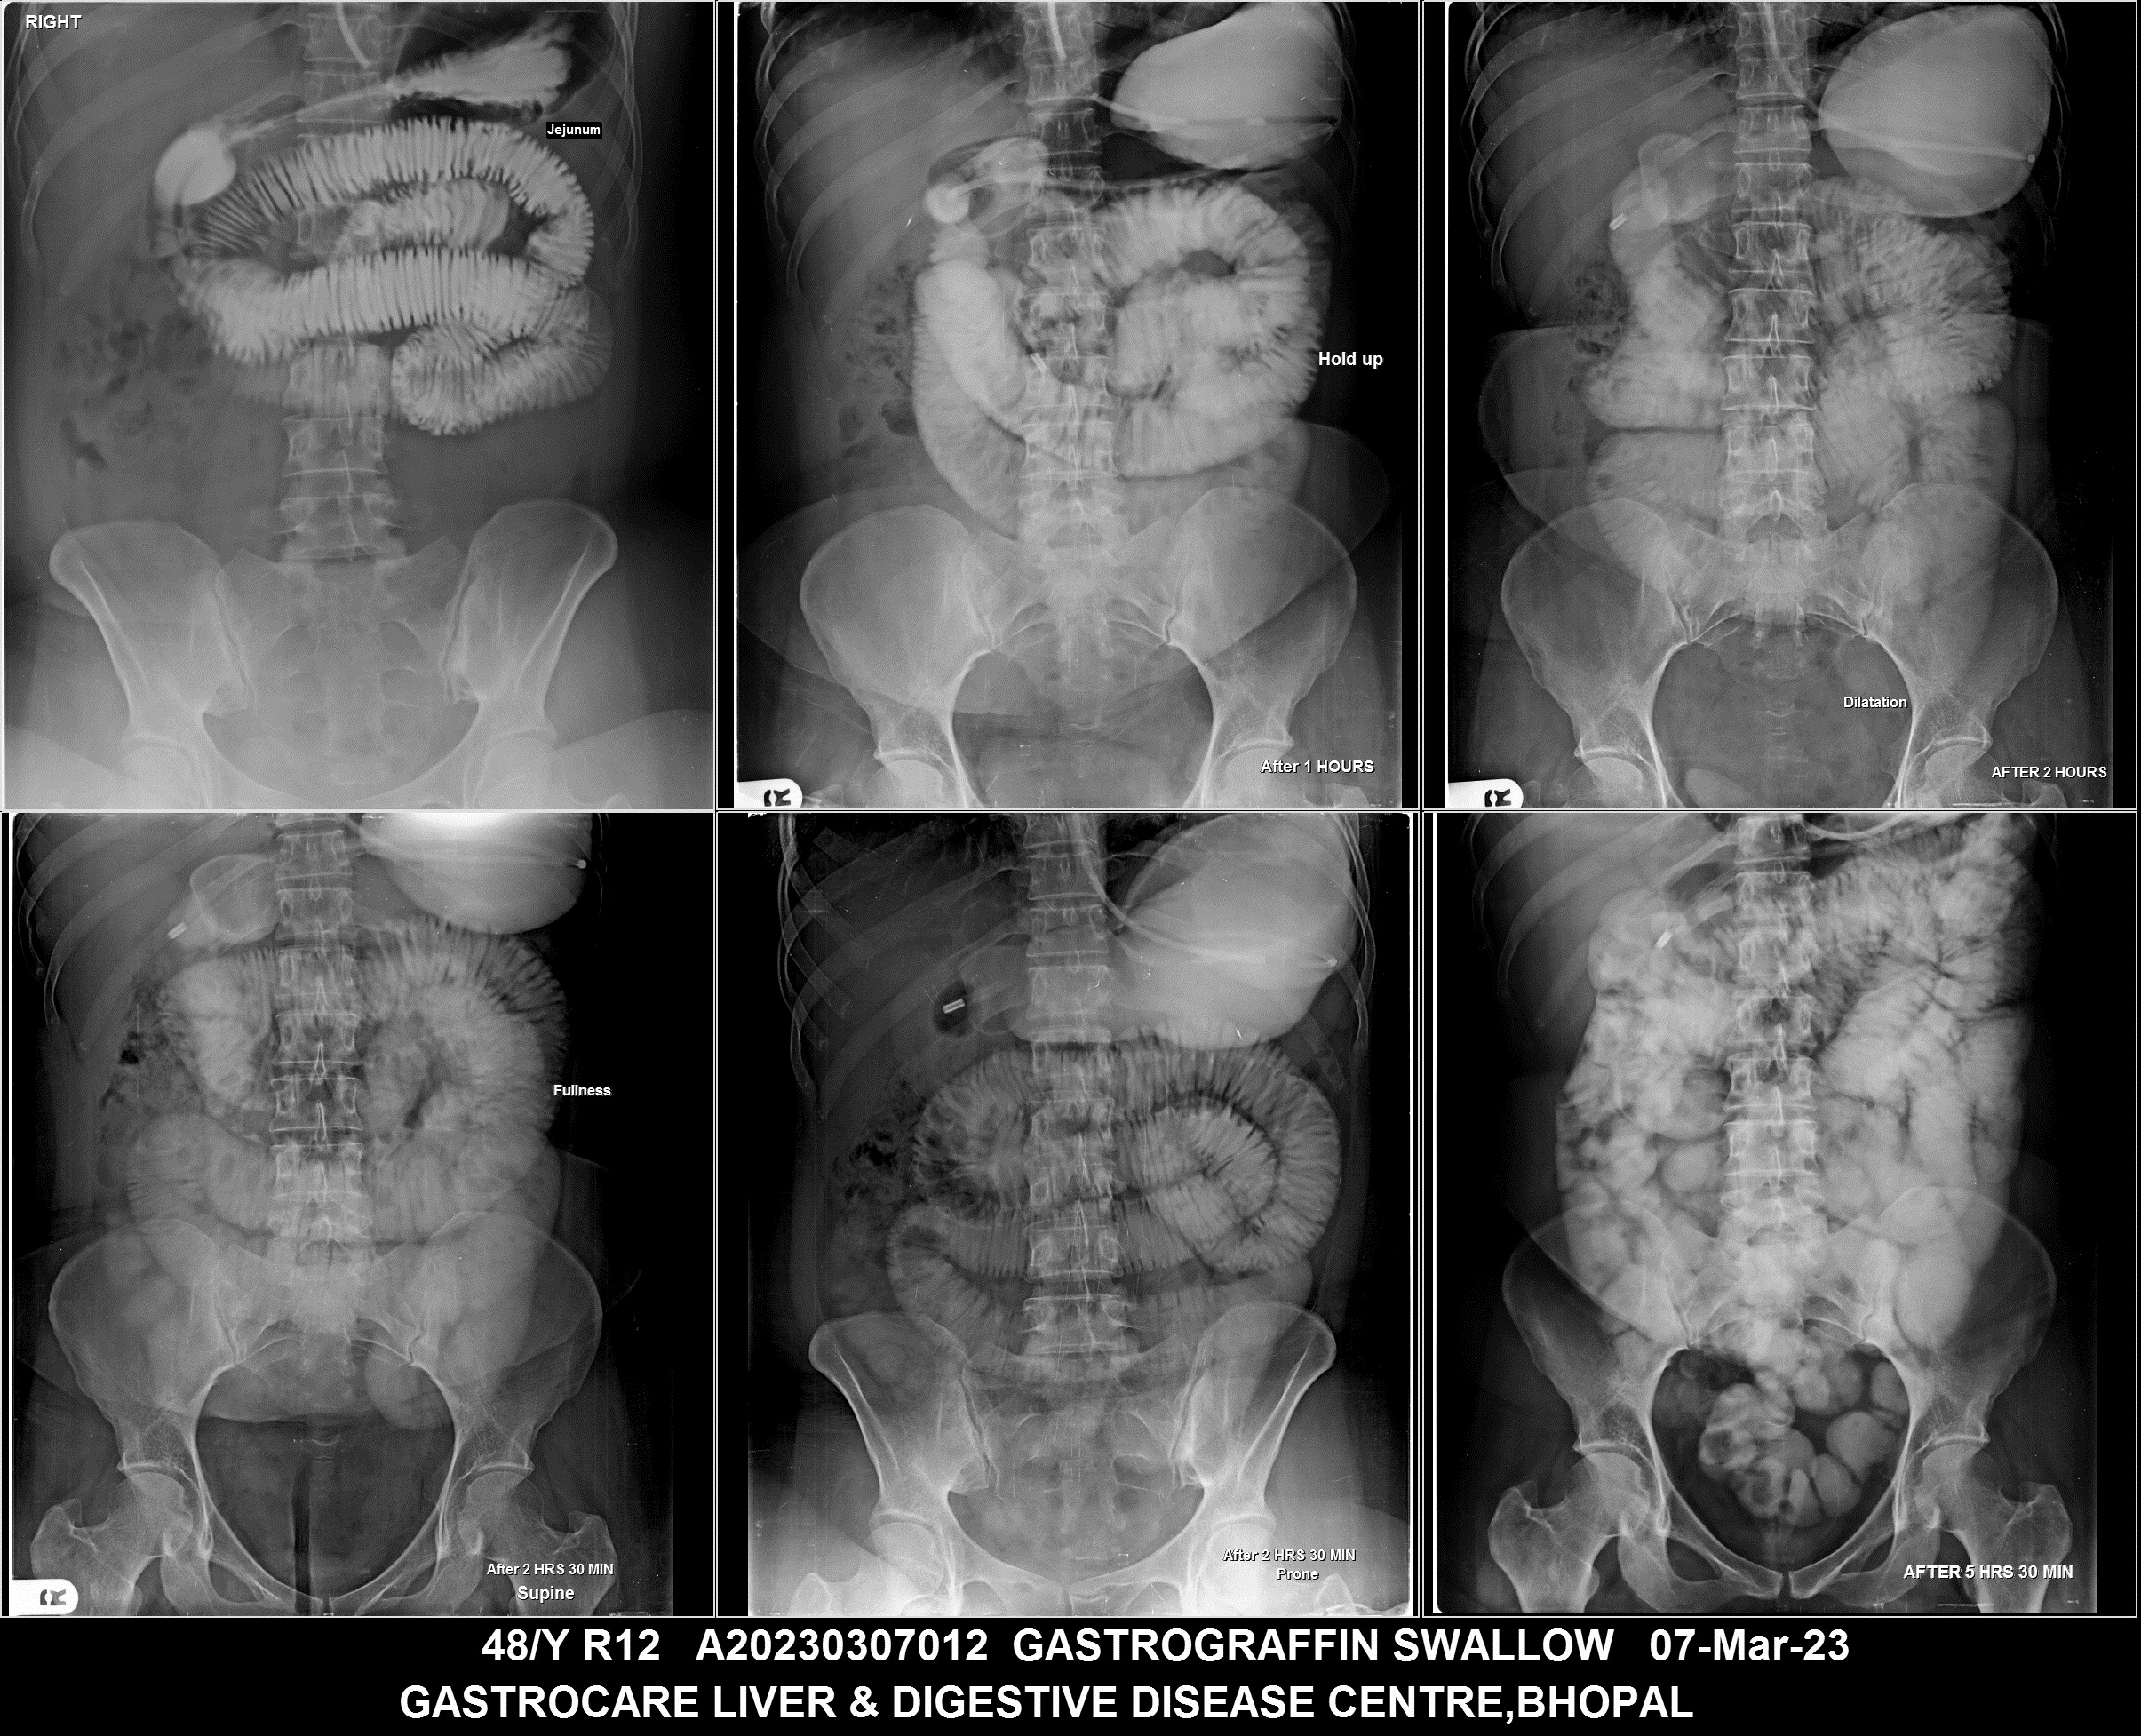

Section: BAM Total: 43 images

BaM Enteroclysis Loopogram BaE Fistulogram Urethrogram HSG